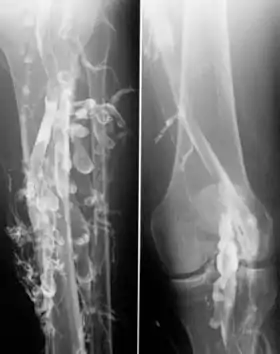

![]() Phlebography in a patient with deep venous thrombosis | |

Contrast venography is the gold standard for judging diagnostic imaging methods for deep venous thrombosis; although, because of its cost, invasiveness, and other limitations this test is rarely performed.[1]